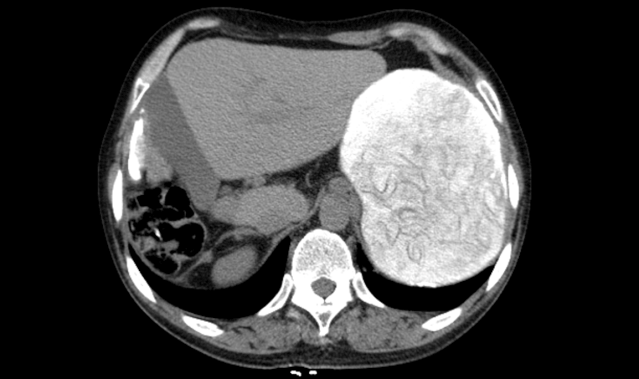

蔣宗華主任憑借多年對肝包蟲病發(fā)展過程中的研究分析了解,結(jié)合患者病情及相關(guān)檢查后,考慮該患者雖然既往做過包蟲手術(shù)造成肝右葉部分缺如,現(xiàn)再次復(fù)發(fā)巨大肝包蟲,位置且在肝胃間系間呈現(xiàn)巨大橢圓形高密度,邊界清晰,大小約148mm*100mm,手術(shù)難度大,風(fēng)險高,但仍有把握完成其“肝包蟲外囊摘除術(shù)”,本著醫(yī)院“患者需求至上”的核心價值觀,西藏阜康醫(yī)院普外科決定收治該患者。

紅色閃動部分為患者肝包蟲區(qū)域